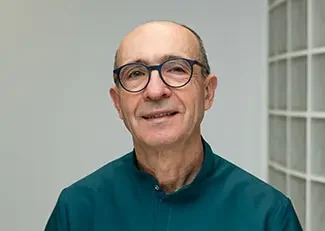

Francisco Javier Elizondo es licenciado en Medicina y Cirugía por la Universidad del País Vasco, especialista en Cirugía Oral y Maxilofacial y especialista en Estomatología. Además, es doctor en Medicina y Cirugía por la Universidad Autónoma de Barcelona. A lo largo de su trayectoria profesional, el doctor Elizondo ha sido profesor asociado en la facultad de Odontología de la Universidad de Barcelona, ha participado en la publicación de distintos libros y artículos sobre Cirugía Oral y Maxilofacial y ha realizado diversas rotaciones en hospitales de Europa y Estados Unidos.